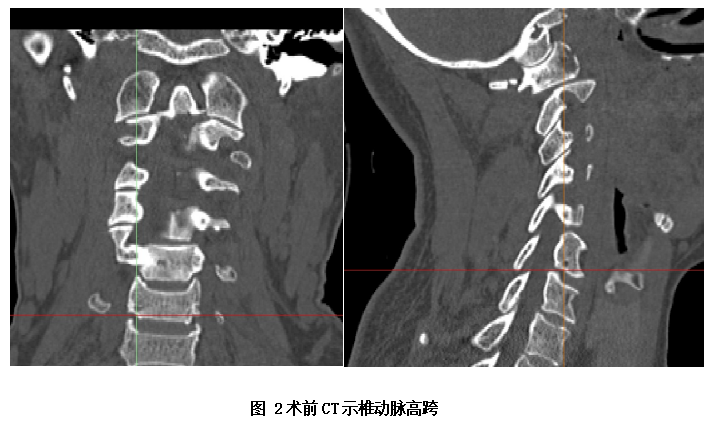

若采用手术方式有利有弊,好处是手术成功后,患者就能较快恢复,及时解决患者的病痛,同时还能避免患者长期卧床、颅骨牵引的痛苦及骨折不愈合的风险。不利是手术风险较大,患者有可能下不了手术台,因为上颈椎(即寰枢椎)手术为脊柱骨科最高风险手术之一,被称为脊柱外科手术上的明珠。因颈部后方显露位置深在,椎管内为延髓,椎弓旁边有椎动脉,任何操作失误都将造成严重后果甚至危及生命,同时该类手术对麻醉、体位及手术操作都有特高的要求。且通过CT片发现,患者还存在椎动脉高跨,极大地增加了手术风险及难度。

面对患者和家属的信任、期待,岳池中医院骨伤科脊柱团队也高度重视该手术。为了减轻患者痛苦及预防相关并发症,促进患者快速康复,经骨伤科全科讨论,决定由脊柱专业组周中伦副主任医师及陈仕文主治医师共同主刀为患者进行手术治疗。在完善相关术前检查排除手术禁忌的条件下,该团队为患者精心设计了手术方案。且为进一降低手术风险,陈医师发挥自已的专业特长,为患者进行了上颈椎的3D模型重建及钉道设计;考虑到枢椎的椎动脉高跨情况,特别为患者设计并制作了枢椎的3D打印导板以引导植入螺钉。